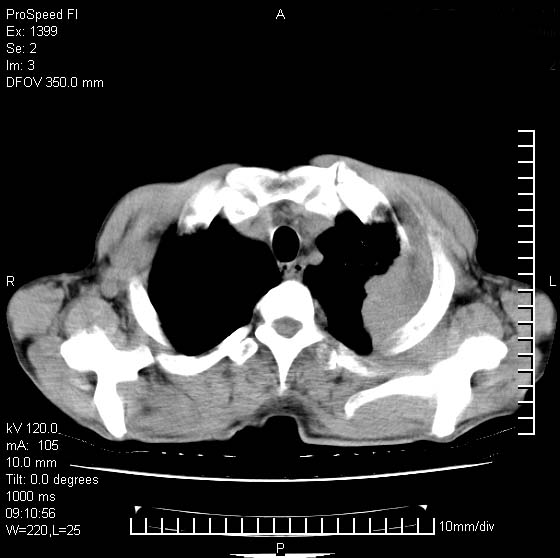

以下是引用卜一在2007-1-19 9:55:00的发言:[br]左肺沿胸膜下巨大肿块影,边缘呈分叶征,纵隔内见肿大淋巴结,右肺内另见一不规则结节影 .考虑:左肺周围性肺癌伴纵隔 右肺内转移.

以下是引用rgsyyf在2007-1-19 11:05:00的发言:[br]左肺上叶见形态不规则巨大软组织肿块影,边缘呈分叶征,纵隔内隆突下见肿大淋巴结,右肺内另见一不规则结节影 .考虑:左肺周围性肺癌伴纵隔即右肺内转移.